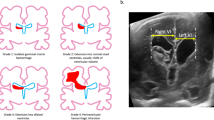

A widely used classification scheme is based on imaging findings and stratifies the degree of hemorrhage and subsequent ventricular dilatation [88]:

-

Grade I: GMH only (subependymal)

-

Grade II: GM-IVH (intraventricular extension without dilatation)

-

Grade III: GM-IVH (intraventricular extension with dilatation)

-

Grade IV: GM-IVH (intraventricular extension with dilatation plus parenchymal hemorrhage)

This system is mainly ultrasound based and can be adapted for computed tomography (CT) and magnetic resonance imaging (MRI) use as well. Ventricular dilatation and parenchymal hemorrhage are described as imaging findings with no pathophysiological correlation, although the higher grades pose higher morbidity and mortality rates. Infants with PHH have a significantly higher mortality rate than low BW infants without PHH (16–35% vs 6.5–13%). Grade I hemorrhage has 5% mortality rate and 5% chances for progressive ventriculomegaly, grade II has 10% and 20%, grade III has 20% and 55%, and grade IV has 50% and 80%, respectively [68].

Long-term neurodevelopmental outcome of infants suffering from GM-IVH has been and still is an important topic of research in pediatric literature. Major issues under investigation are the extent of hemorrhage (grade), coexistent parenchymal injury (Fig. 3), and progression of compensated ventriculomegaly. The severity of GM-IVH, as determined by its grade, is an important factor for the mortality rate. Neurological disabilities are mainly influenced by the presence and extent of the parenchymal injury [117, 118]. Spasticity and intellectual deficits result from posthemorrhagic infarction, while PVL is mainly responsible for spastic diplegia, typically more severe in the lower than in the upper limps [68]. Mental retardation, seizures, and cerebral palsy are the most frequent disabilities. The timing of GM-IVH seems to affect neurodevelopmental outcome as infants who develop hemorrhage in <6 h of life have more chances to suffer from cerebral palsy and lower IQ scores [118]. Follow up should extend to childhood or even adolescence in order to unveil minor cognitive and neuropsychological deficits.

Assessment of brain damage following neonatal IVH with MR scan late after the event. a T1w axial MR scan of a 5-year-old boy who suffered grade IV IVH at birth. A large area of porencephaly is seen in the left frontal lobe, as the parenchyma surrounding the left frontal horn was destroyed following the initial hemorrhage, which had as its epicenter probably the head of the caudate nucleus, and the area was filled with ventricular CSF. b T1w axial MR scan of a 2-year-old girl who suffered a grade IV IVH at birth. The area surrounding the left occipital horn has suffered necrosis and cystic change, secondary to the initial insult. The child required shunting